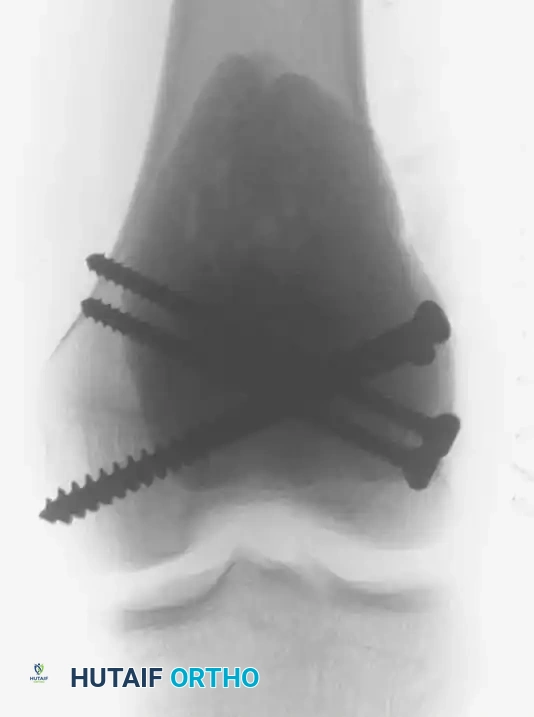

6. Structural Augmentation (Rebar Technique)

- Because the subchondral bone plate is often paper-thin following aggressive curettage, packing PMMA directly against it can lead to thermal injury to the articular cartilage or mechanical point-loading.

- To prevent this, structural cortical screws are placed across the cavity. These act as "rebar," distributing the mechanical load from the joint surface into the diaphyseal cortical bone.

Intraoperative photograph showing the placement of multiple structural screws within the cavity to support the subchondral plate and anchor the cement mantle.

Intraoperative fluoroscopy confirming the optimal trajectory and depth of the structural screws, ensuring they do not breach the articular surface.

7. Cementation (PMMA Application)

- The tourniquet is temporarily deflated to ensure hemostasis, then re-inflated. The cavity is thoroughly irrigated and dried.

- Standard viscosity PMMA bone cement is introduced into the cavity in a doughy state. It is digitally packed firmly around the screws and into all crevices of the burred cavity to ensure a perfect interdigitation with the host bone.

Postoperative Anteroposterior (AP) and Lateral radiographs demonstrating the final reconstruction. The radiopaque cement mantle and structural screws provide immediate stability.